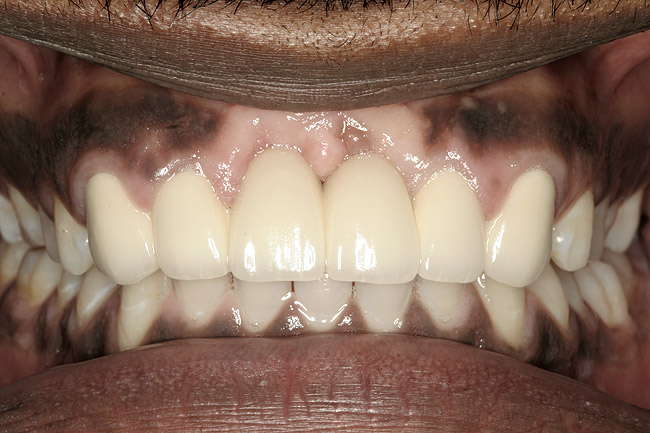

The decision to retain or extract a questionable tooth is one that occurs frequently in dental practice. There are many factors to consider when making this decision. Some situations are very straightforward (Figure 1) while others fall into a “gray” area of decision-making (Figure 2). This article will provide guidelines for determining whether to extract or retain a tooth when the decision is not so straightforward using structural, periodontal, endodontic, and esthetic criteria. Some teeth may involve only one of these areas, and some will involve various combinations of these areas. There are also other important factors to consider such as patient expectations, patient finances, and patient compliance, but these topics vary from patient to patient and should be discussed with each individual patient. While these topics are very important to the decision-making process, they are beyond the scope of this article.